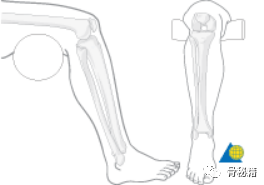

将大脚趾与髌骨保持一致来近似旋转对准,

保持了胫骨的正常轻微外旋。

踝关节背伸90度。

评估胫骨旋转对准的最佳方式,

是通过大腿和脚的长轴之间的角度。

如果旋转复位是正确的,

则脚的长轴相对于大腿的轴稍微向外旋转。

这个足-大腿角应该与相对的下肢相同。